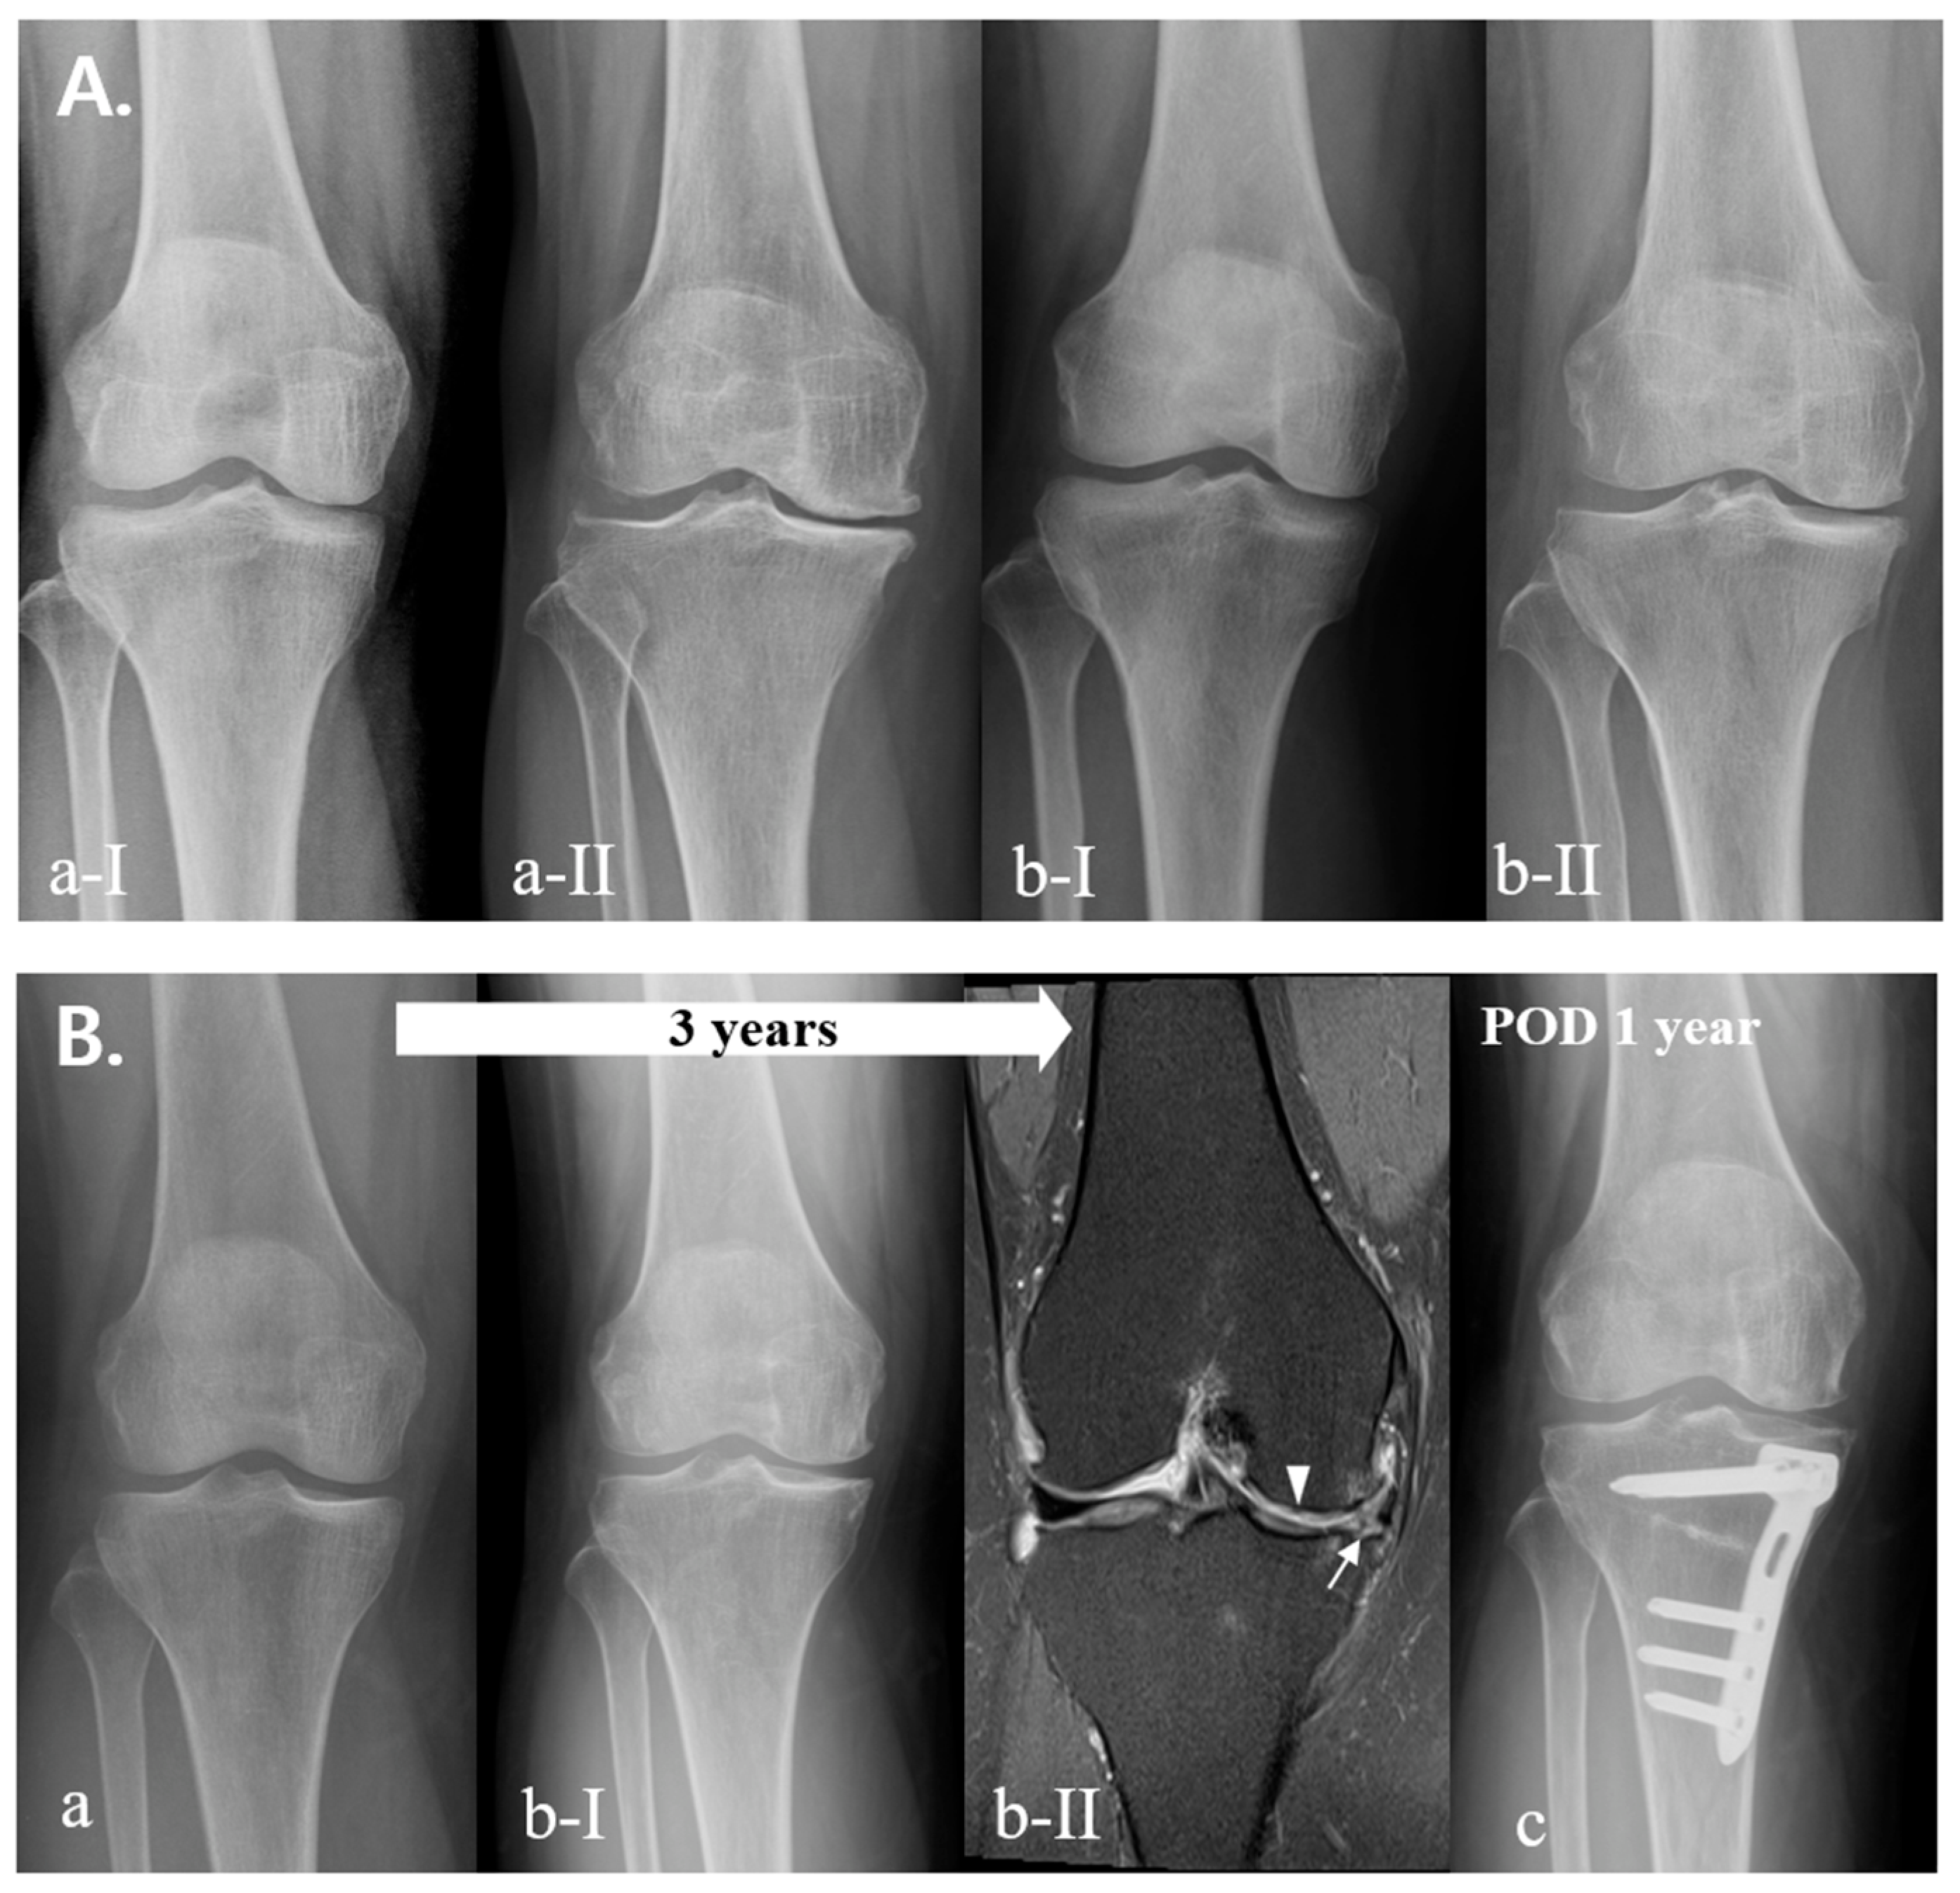

2.1. Classification

3. Results

4. Discussion